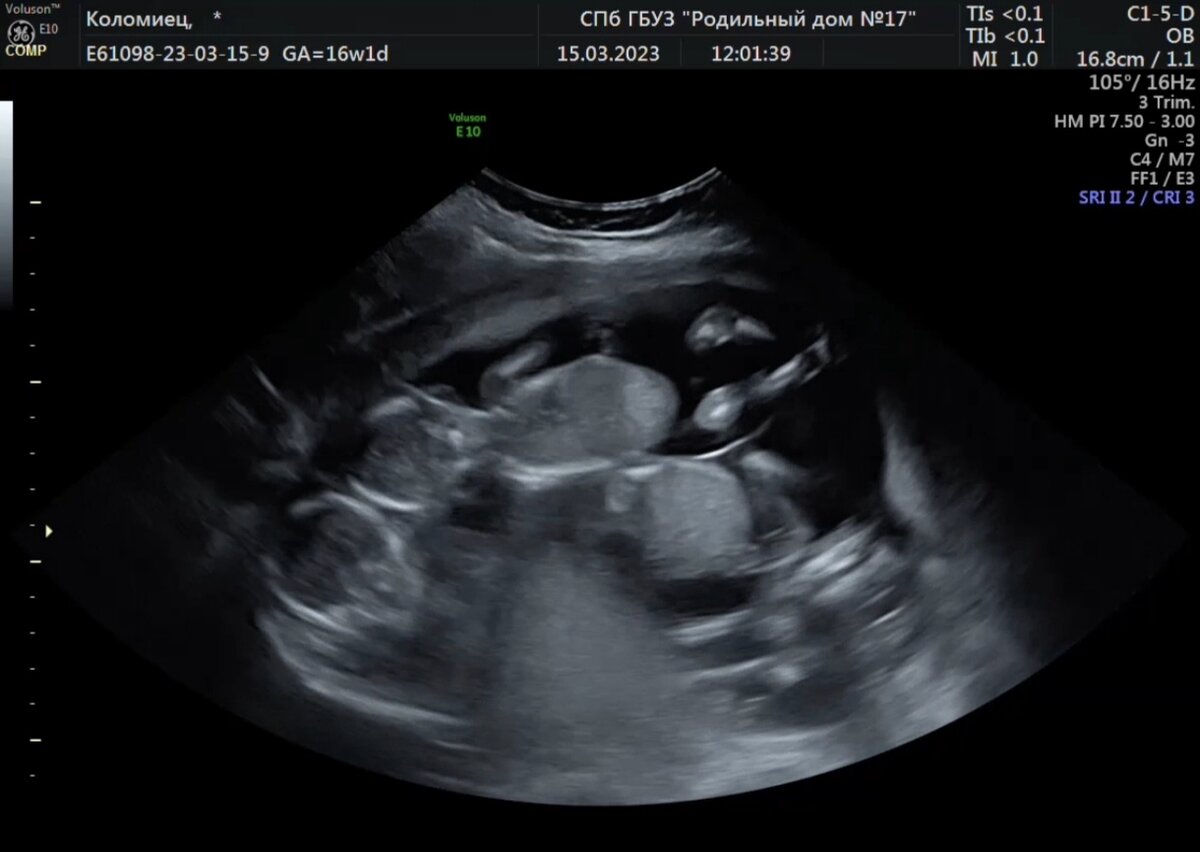

Врач несколько секунд молчит, водит по животу. Меня сковал ужас, не передать. Я еще не пришла в себя от этого вопроса, как меня накрыли следующие ее слова "У вас там трое"...тишина. Что? у меня просто оборвалось все внутри, слезы градом, я умоляю ее так не шутить. Я не верю в происходящее. Рыдаю и не верю. Это какой-то дешевый сериал, в котором могут быть такие повороты, мне все кажется нереальным, глупым и наигранным. Такого не бывает в жизни. Нет! нет! и еще раз нет! Этого просто не может быть и точка, сейчас я проснусь и мы посмеемся с мужем над этим глупым сном. Попросила даже меня ущипнуть, чтобы поскорее проснутся, она посмотрела на меня, как на сумасшедшую. Потом развернула ко мне монитор. "Вот смотрите, их там трое, вижу, что два точно мальчики, продолжает она...а третий скромно отвернулся и пол не видно."

Трое в животе